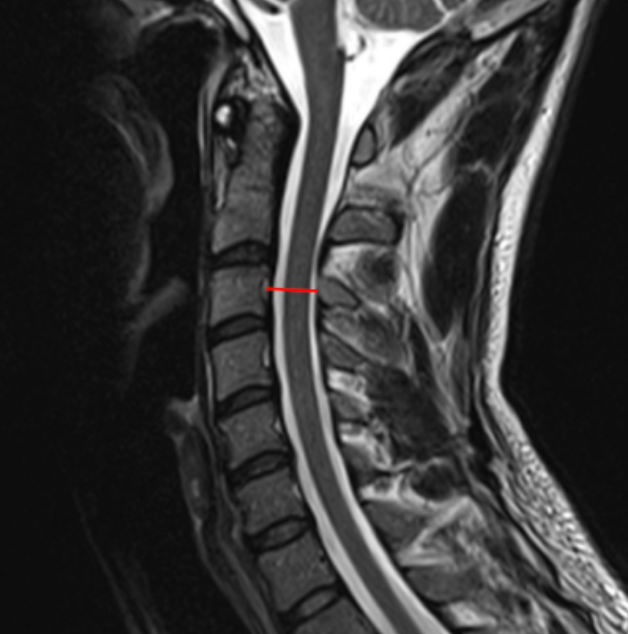

Image Type Cervical Spine X-Ray CT Scan MRI Scan Compression Ratio (AP diameter transverse diameter of cord) Cord Cross-Sectional Area (CSA) Cross-Sectional Canal Area Maximum Spinal Cord Compression Pavlov/Torg (Canal-Body Ratio) Sagittal Canal Diameter Spinal Cord Signal Change - T1 Hypointensity Spinal Cord Signal Change - T2 Hyperintensity (+ number of levels)